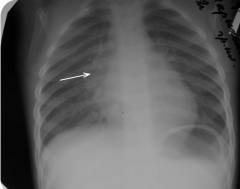

- Туморозная форма – самая тяжелая, затрагивает все группы узлов, размеры превышают 20 мм. Преобладают экссудация и казеоз, возможны осложнения, такие как прорыв гноя в бронхи или ателектаз. Рентгенограмма ребенка 2-х лет. Диагноз: инфильтративная форма туберкулеза внутригрудных лимфатических узлов. Легочные поля без патологий, расширение корня легких справа из-за увеличенных лимфоузлов.

Эти компоненты взаимосвязаны.Обзорная рентгенограмма органов грудной полости ребенка 3-х лет. Диагноз: двусторонний первичный туберкулезный комплекс. На рентгенограмме в верхних долях обоих легких видны очаги инфильтрации, связанные с увеличенными корнями легких.